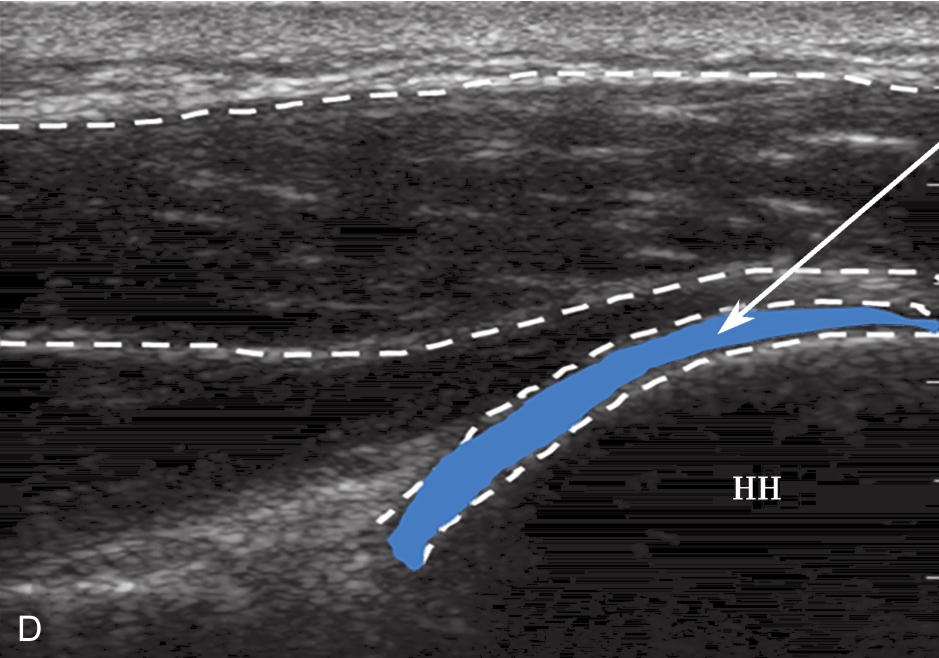

▲ 图2-6-4 超声引导下肩关节腔介入治疗超声图(二)

A.肩关节下关节囊增厚;B.超声引导下穿刺针进入盂肱关节腔

▲ 图 2-6-4(续)

C.超声引导下类固醇及生理盐水注射;D.注射治疗后关节腔扩张;双星号:增厚关节囊;箭头:穿刺针;单星号:关节腔